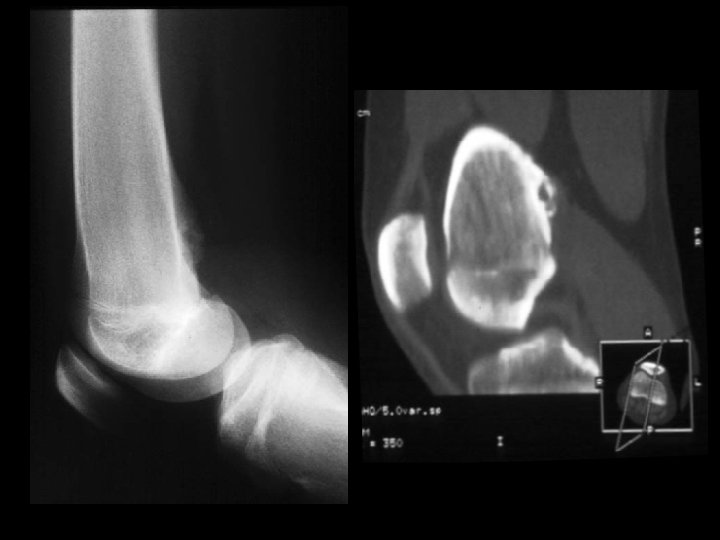

Hemangioma • Findings: – expansile lesion of the proximal tibia containing fine bony septations and a large course calcification – CT scan shows a lacey appearance • ddx: – Paget’s dz – ABC